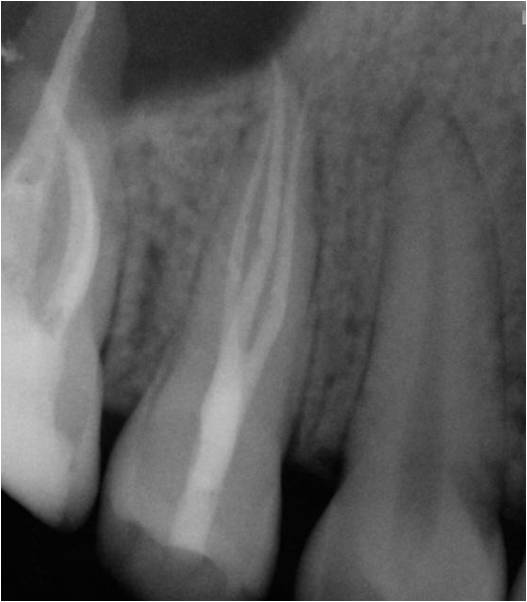

Excellent diagnosis essentially begins with two fundamental components: a doctor willing to listen to the patient’s chief complaint, and proper diagnostic tools. Among the most important tools are a precise periapical radiograph (PA) and bitewing (BW). Although a PA is often enough to provide an accurate portrayal of the patient’s condition, sometimes it alone does not suffice. Figure 1, Figure 2, and Figure 3 demonstrate a case that illustrates this point clearly. Despite two acceptable PAs (Figure 1 and Figure 2), it is difficult to assess the source of the patient’s pain to temperature. However, the BW radiograph Figure 3 provides significantly more clarity than either of the two PAs. The BW depicts localized bone loss (around tooth No. 2), a pulp stone (No. 2), a flat occlusion, numerous calcified canals, multiple restorations in tooth No. 30, and gross decay especially on tooth No. 3, which is the source of the patient’s pain to temperature. In this instance these images depict how much more useful a BW can be than just a conventional PA.

Fig 1. Foreshortened PA radiograph.

Figure 1

Fig 2. Acceptable PA radiograph.

Figure 2